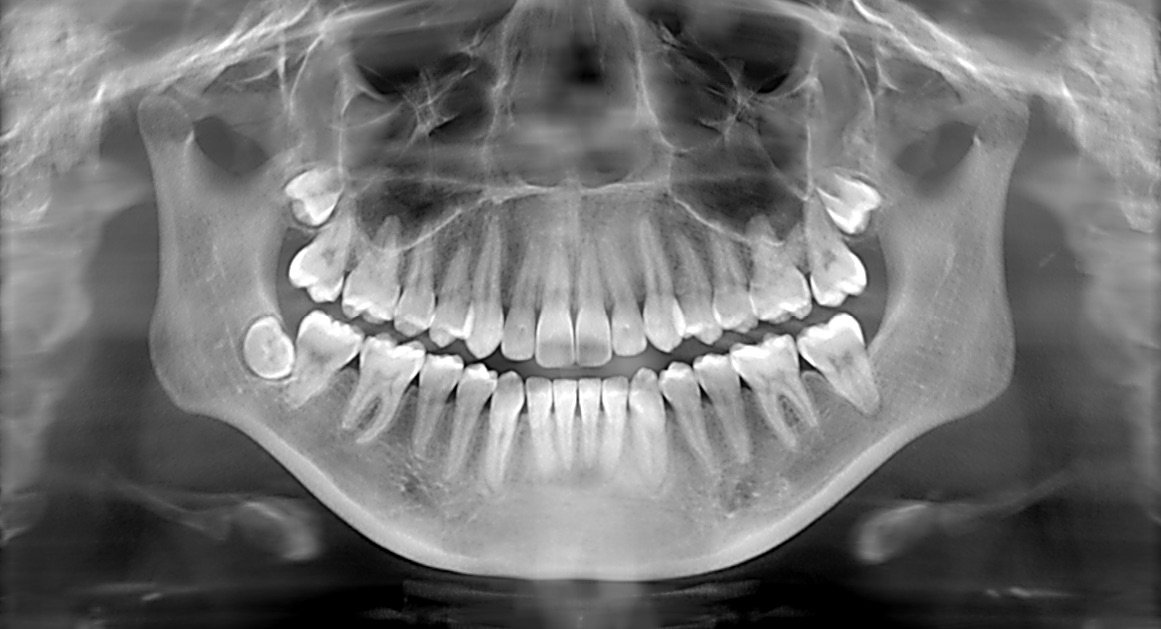

Understanding Radiology: Focus on Intraoral Periapical Radiography (IOPA)

Radiology plays a crucial role in modern medicine and dentistry, providing essential insights into the human body through various imaging techniques. Among these, intraoral periapical radiography (IOPA) is a fundamental method utilized in dental practices to diagnose and manage oral health conditions. This article explores the significance of radiology in dentistry, with a particular focus on IOPA, its applications, benefits, techniques, and the related radiology dental services offered.

The Role of Radiology in Dentistry

Radiology in dentistry involves the use of imaging technologies to visualize the structures of the teeth, jaws, and surrounding tissues. It aids in diagnosing dental diseases, planning treatments, and monitoring the outcomes of procedures. The primary types of dental radiographs include:

- Periapical Radiographs: Capturing the entire tooth structure, including the root and surrounding bone.

- Bitewing Radiographs: Focused on the crowns of the upper and lower teeth, useful for detecting cavities and monitoring interproximal areas.

- Panoramic Radiographs: Providing a broad view of the jaws, teeth, and surrounding structures in a single image.

- Cone Beam Computed Tomography (CBCT): Offering three-dimensional imaging, crucial for complex cases such as implants and orthognathic surgery.

Intraoral Periapical Radiography (IOPA)

What is IOPA?

Intraoral periapical radiography (IOPA) is a specific type of dental X-ray that focuses on the periapical region of a tooth. It captures detailed images of the tooth, including the crown, root, and surrounding bone, making it invaluable for diagnosing various dental conditions.